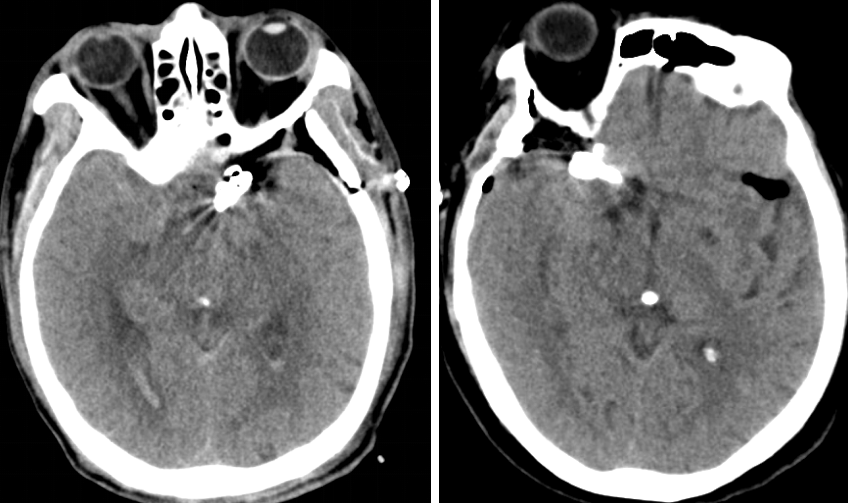

头颅CT

头颅MRI